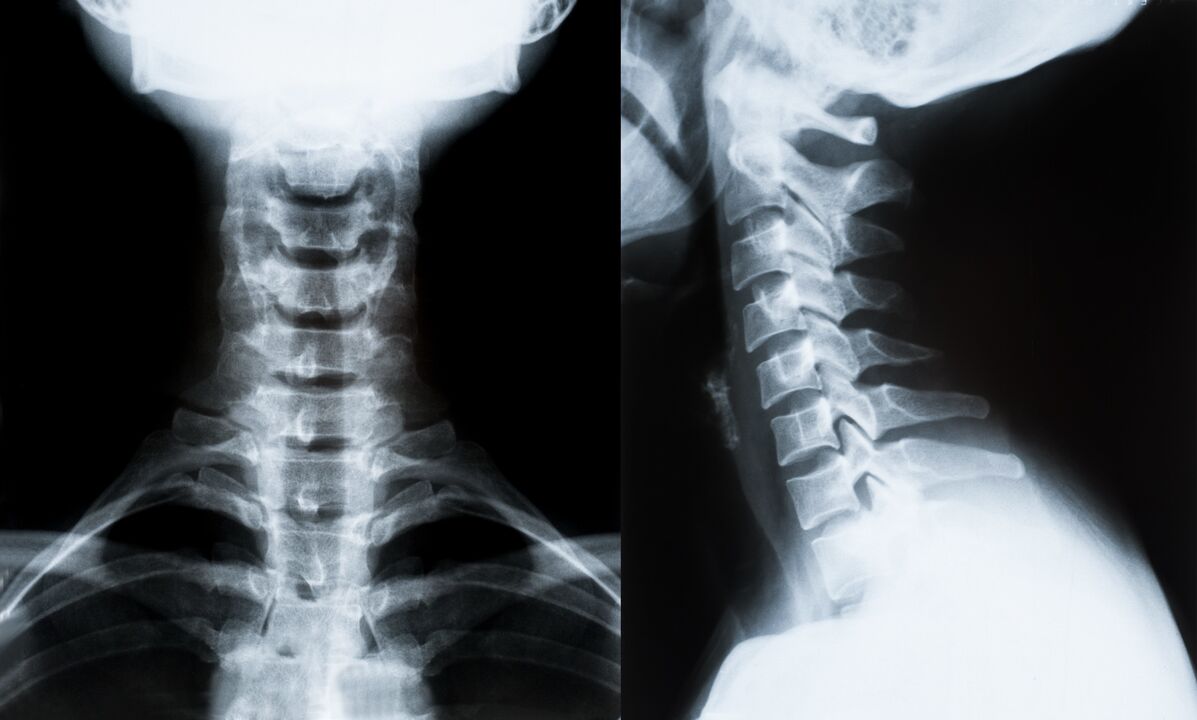

Os principais métodos de diagnóstico e determinación adicional do tratamento da osteocondrose da columna cervical:

- radiografía. O método de diagnóstico menos efectivo, pero tradicional.

- A resonancia magnética é o método diagnóstico máis eficaz. Con este tipo de exame do paciente, todas as estruturas necesarias son visibles.

- Se hai que medir cambios, úsase tomografía computarizada. Determina a presenza de hernias e outras cousas.

- O último método é a exploración dúplex de ultrasóns. Este método de investigación determina a velocidade do fluxo sanguíneo nas arterias.

É imposible determinar con precisión a enfermidade da columna na casa.